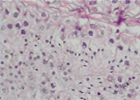

Hình 2. Sinh thiết tinh hoàn: ống sinh tinh với nhiều tinh trùng trưởng thành. |

Phân loại mô học sinh tinh của Levin thường được sử dụng 3, dựa trên việc phân tích khả năng sinh tinh của mô tinh hoàn với năm mức độ như sau: xơ hóa các ống sinh tinh (thoái hóa hyalin), hội chứng toàn tế bào Sertoli, ngừng sinh tinh nửa chừng, giảm sinh tinh và sinh tinh bình thường. Trong trường hợp vô tinh không bế tắc với tinh hoàn teo nhỏ, nồng độ FSH cao, khả năng trích được TT lần lượt là 79%, 47% và 24% trong giảm sinh tinh (hypospermatogenesis), ngừng sinh tinh nửa chừng (maturation arrest) và hội chứng toàn tế bào Sertoli (Sertoli-cell-only syndrome), theo Seo 9. Trong nghiên cứu này, chúng tôi có một trường hợp trích được TT bằng microTESE và điều đặc biệt là trường hợp này sinh thiết tinh hoàn trước đó là thoái hóa hyalin. Trên đại thể, tinh hoàn của bệnh nhân toàn mô xơ trắng nhạt (phù hợp với kết quả giải phẫu bệnh là thoái hóa hyalin) và chỉ có vài điểm có mô màu vàng tươi, với các ống sinh tinh giãn to, có TT trưởng thành bên trong. Các TT này đã được sử dụng để thực hiện TTTON cho vợ bệnh nhân với kỹ thuật ICSI.